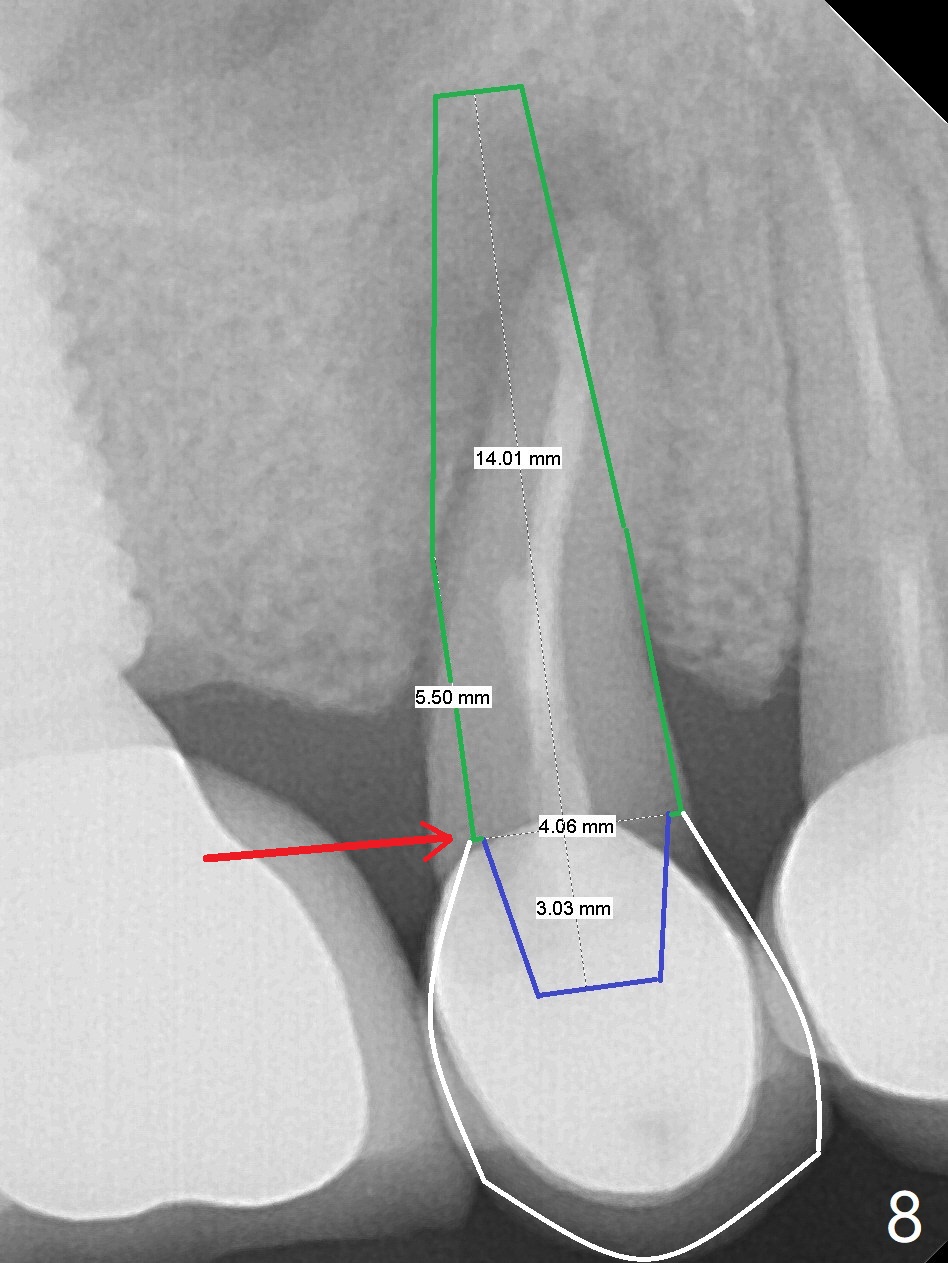

Crown/Implant Ratio

A 53-year-old man has signs of bruxism (Fig.1 diastema *) and root fracture or RCT failure at #4 (Fig.4 (large PARL *)). The RCT failure is related to overload of the affected tooth, which is in turn partially due to infraocclusion of the neighboring implant crown (Fig.1 arrows (implant positioning not ideal)) and partially to due to partial edentulism (Fig.2 missing teeth #14 and 18). For long term, limited ortho will be performed to upright and distalize the tooth #15 (Fig.3 arrow), followed by implants at #14 and 18. For now, the tooth #4 will be extracted (Fig.5), followed by osteotomy in the distal slope of the socket with guide (Fig.6 to get good trajectory). To place a bone-level implant (Fig.7 green), an abutment (blue) with long cuff (pink) is to be used. With poor implant/crown (white) ratio, stress occurs at the junction of the implant/abutment (red arrow), resulting in easy abutment screw loosening. In contrast, stress may be applied to directly to a tissue-level implant (Fig.8 arrow) with less likelihood of abutment screw loosening. The implant/crown ratio improves by approximately 5.5 mm. The roots of the teeth #15 and 16 are so close to each other that interference may occur when the tooth #15 is being uprighted (Fig.9). The empty socket of the tooth #4 is wide buccopalatal (Fig.10); the buccal plate is resorbed coronally (Fig.10 <) so that a 4.5 or 5 mm diameter implant should be placed palatal (Fig.11). Use sticky bone to repair the buccal plate defect and PRF membrane or plug for sinus lift. Following #15 uprighting and distalization, a 5x10 mm implant will be placed at #14; the ridge is triangular (Fig.12 <) so that bone trimmer is needed. A 10 mm long implant will be placed at #18 (Fig.14) to avoid perforating to the submandibular fossa (Fig.13 *).